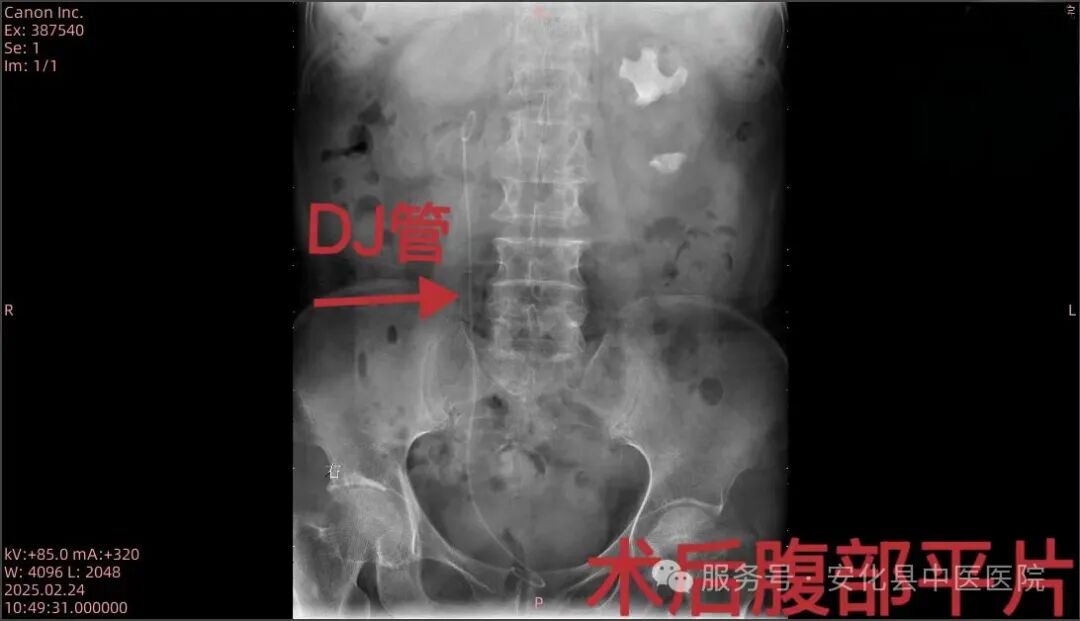

患者,女,70岁,因“右侧腰腹部疼痛不适2天”入住我院泌尿外科,泌尿系CT检查提示“右肾多发性结石并右肾中度积水、右侧输尿管多发性结石、左肾多发性结石”。为减少创伤,保护患者肾脏功能,泌尿外科主任朱武、主治医师邓智勇多次研究讨论该病例治疗方案,最终决定行右侧经尿道可弯曲负压吸引鞘+输尿管软镜下钬激光取石术,术后患者恢复良好。输尿管鞘是什么【技术突破】无创取石新利器——安化县中医医院成功开展可弯曲负压吸引鞘联合输尿管软镜钬激光碎石取石术•“卓越服务”系列报道(十六)_https://www.jmylbn.com_新闻资讯_第3张输尿管鞘是什么【技术突破】无创取石新利器——安化县中医医院成功开展可弯曲负压吸引鞘联合输尿管软镜钬激光碎石取石术•“卓越服务”系列报道(十六)_https://www.jmylbn.com_新闻资讯_第4张

▲术前术后腹部平片对比